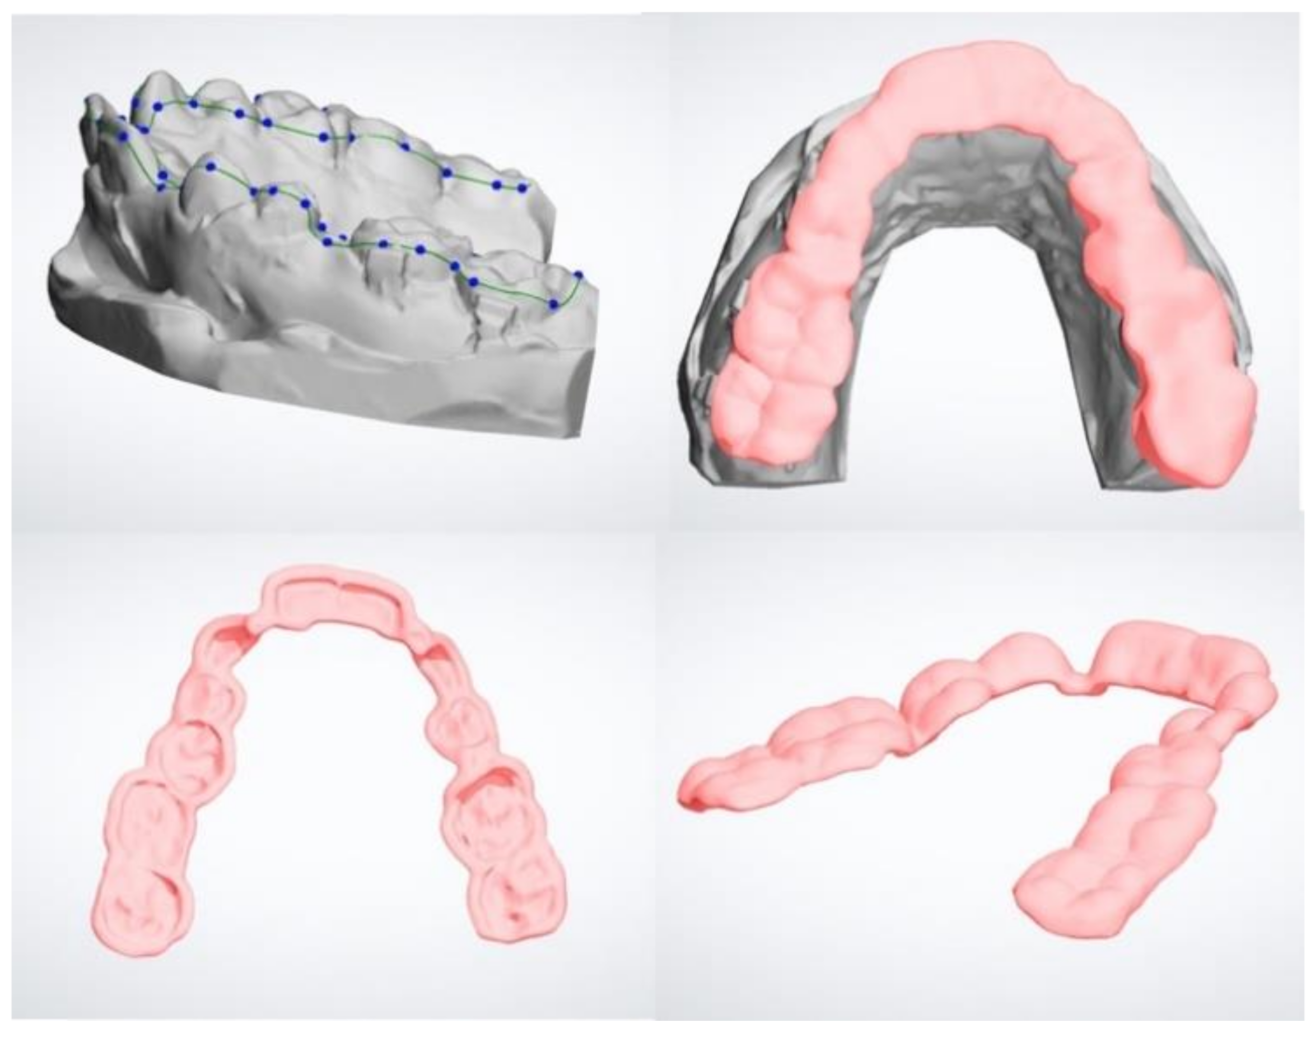

2. Materials and Methods

3. Results